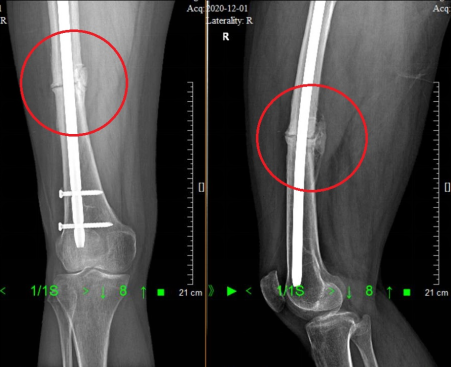

47岁的佛山李女士,5年前摔伤引发右股骨中段骨折,接受“右股骨髓内钉内固定术”后能够恢复行走,但多年来复查仍可见骨折断端间隙,在外院经过髓内钉动力化(拆除近端锁定钉)、拆除近端动力钉..